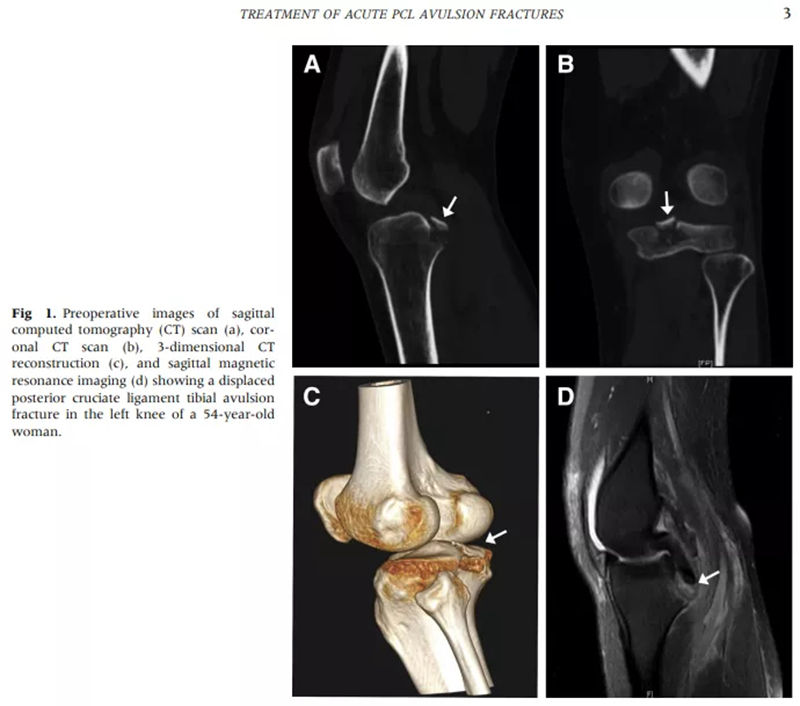

徐醫(yī)附院通過(guò)關(guān)節(jié)鏡微創(chuàng)手術(shù),只需做4個(gè)8mm左右的小切口,通過(guò)做一個(gè)直徑0.45cm、長(zhǎng)約5cm的骨隧道,將長(zhǎng)線(xiàn)環(huán)帶袢鈦板引入關(guān)節(jié)內(nèi),鈦板固定骨折,即可取得很好的穩(wěn)定性,經(jīng)過(guò)長(zhǎng)時(shí)間大規(guī)模的病例累計(jì),形成了40例的總結(jié)分析和評(píng)估,系統(tǒng)地講述了關(guān)節(jié)鏡下微創(chuàng)處理后交叉韌帶撕裂的手術(shù)方式、要點(diǎn)和治療效果,對(duì)行業(yè)發(fā)展也具有很好的借鑒意義。